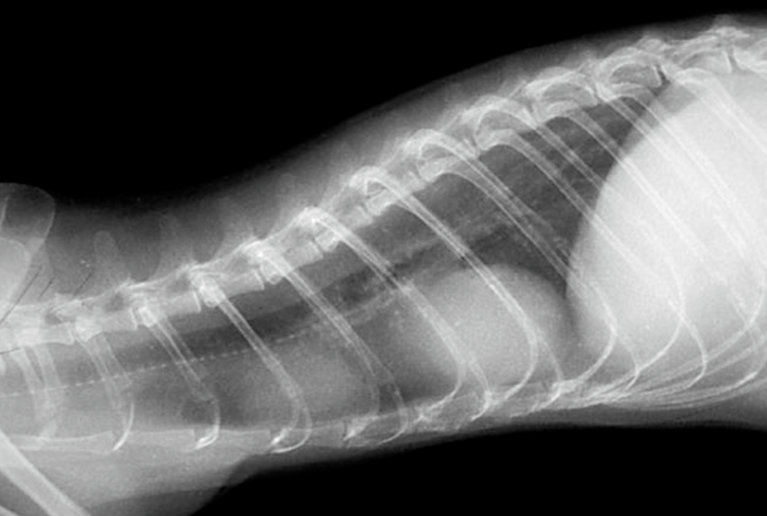

- 縦隔型: 胸腔内の腫瘤(多くは胸腺由来)が肺や心臓、大血管を物理的に圧迫するため、呼吸困難、努力呼吸、咳、および胸水の貯留が見られます 。

確定診断には、リンパ球の異常な増殖を証明するための組織サンプルの採取が不可欠です。 診断的ワークアップとして、血液検査(CBC、血液化学検査)を行い、全貌の確認のために X線検査(特に胸部、縦隔腫瘤や胸水の評価)および腹部超音波検査(腹腔内リンパ節、肝臓、脾臓、消化管の評価)が必須です 。超音波検査は、細胞診や生検のためのサンプル採取のガイドとしても極めて有用です 。さらなる詳細にはCTやMRIも有用です。